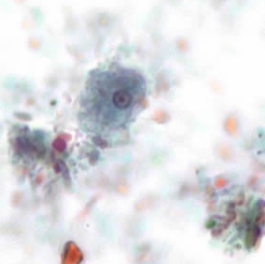

Professor: Dr. Glena Fe A. Yapchulay-Alcabasa

ENTAMOEBA HISTOLYTICA TROPHOZOITE INGESTED RBC